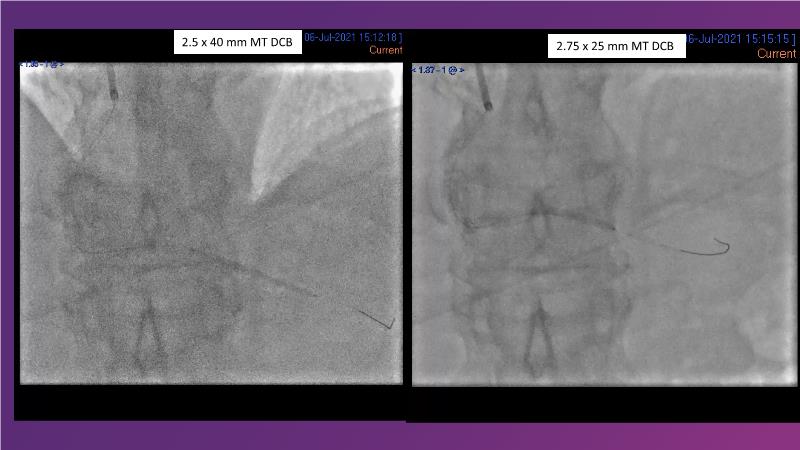

Sirolimus-coated balloon: expanding the scope of indications for complex coronary artery disease treatment

Watch this session to gain case-based insights on using DCBs in complex settings. Learn valuable tips and tricks for optimal DCB application, including the best timing and situations for their use. Discover how to effectively implement a hybrid strategy that combines DES and DCB when needed.

- To get a case based experience on how to use a DCB in complex settings

- To learn about tips and tricks on how and when to use a DCB: the ideal time and situation of DCB application in various complexities